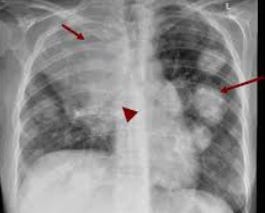

Repurposed Drugs in Oncology: Current State Of The Evidence And A Case Series In Metastatic Lung Cancer

A review of the existing evidence base for repurposing drugs to treat cancer, followed by a case series of five consecutive patients treated with…

Case Series Of Metastatic Lung Cancers Treated With Combination Repurposed Drug Regimens - Short Version

All patients presented herein were seen and treated consecutively to avoid presenting unrealistic or overstated efficacy. Still, the outcomes, in my…